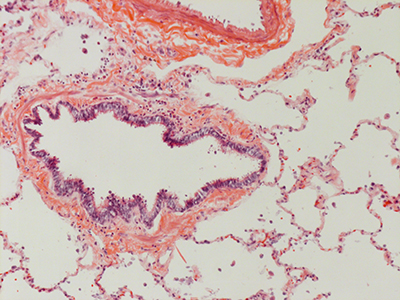

31 Year Old Adult Human Lung DD037 H&E